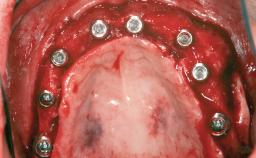

| # of Implants | 1 |

| Bone Augmentation | Staged|Vertical |